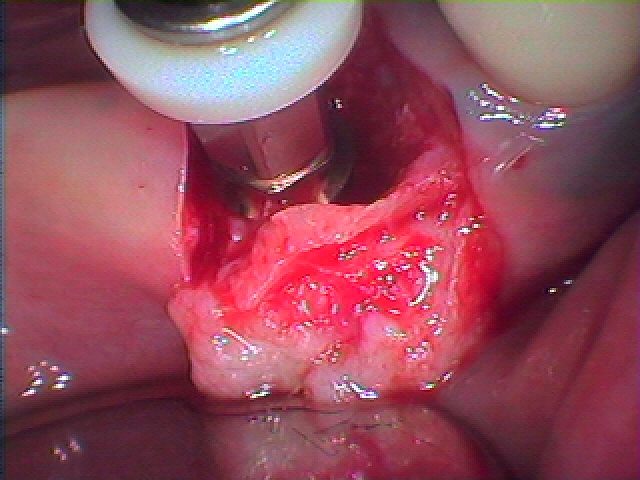

切開して排膿を行っています

近親婚にはヒビが入っており遠心根も分離して厳しい状態でした